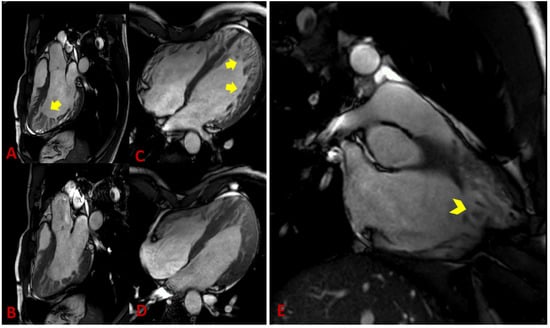

4.2. Magnet Resonance Imaging

| Petersen [42] | CMR | Ratio of compacted epicardium and non-compacted endocardium | End diastole | NC/C ≥ 2.3 |

| Stacey [43] | CMR | Ratio of compacted epicardium and non-compacted endocardium | Short axis, end-systole | NC/C ratio of ≥ 2.0 |

| Jacquier [44] | CMR | A value of trabeculated LV mass above 20% of the global mass of the LV | End diastole | LV trabeculated mass > 20% |

| Grothoff [39] | CMR | Ratio of total LV trabeculated mass to global myocardial mass | End systole | Trabeculated ventricular mass greater than 25% of the global left ventricular mass; noncompacted mass greater than 15 g/m2 |

| Choi [45] | CMR | A percentage of trabeculated myocardial volume of the total myocardial volume of the LV | End-diastole, long-axis | LV trabeculated volume > 35% |

| Captur [46] | CMR | Maximal fractal dimension | End diastole | Global fractal dimension > 1.26; apical fractal dimension > 1.3 |